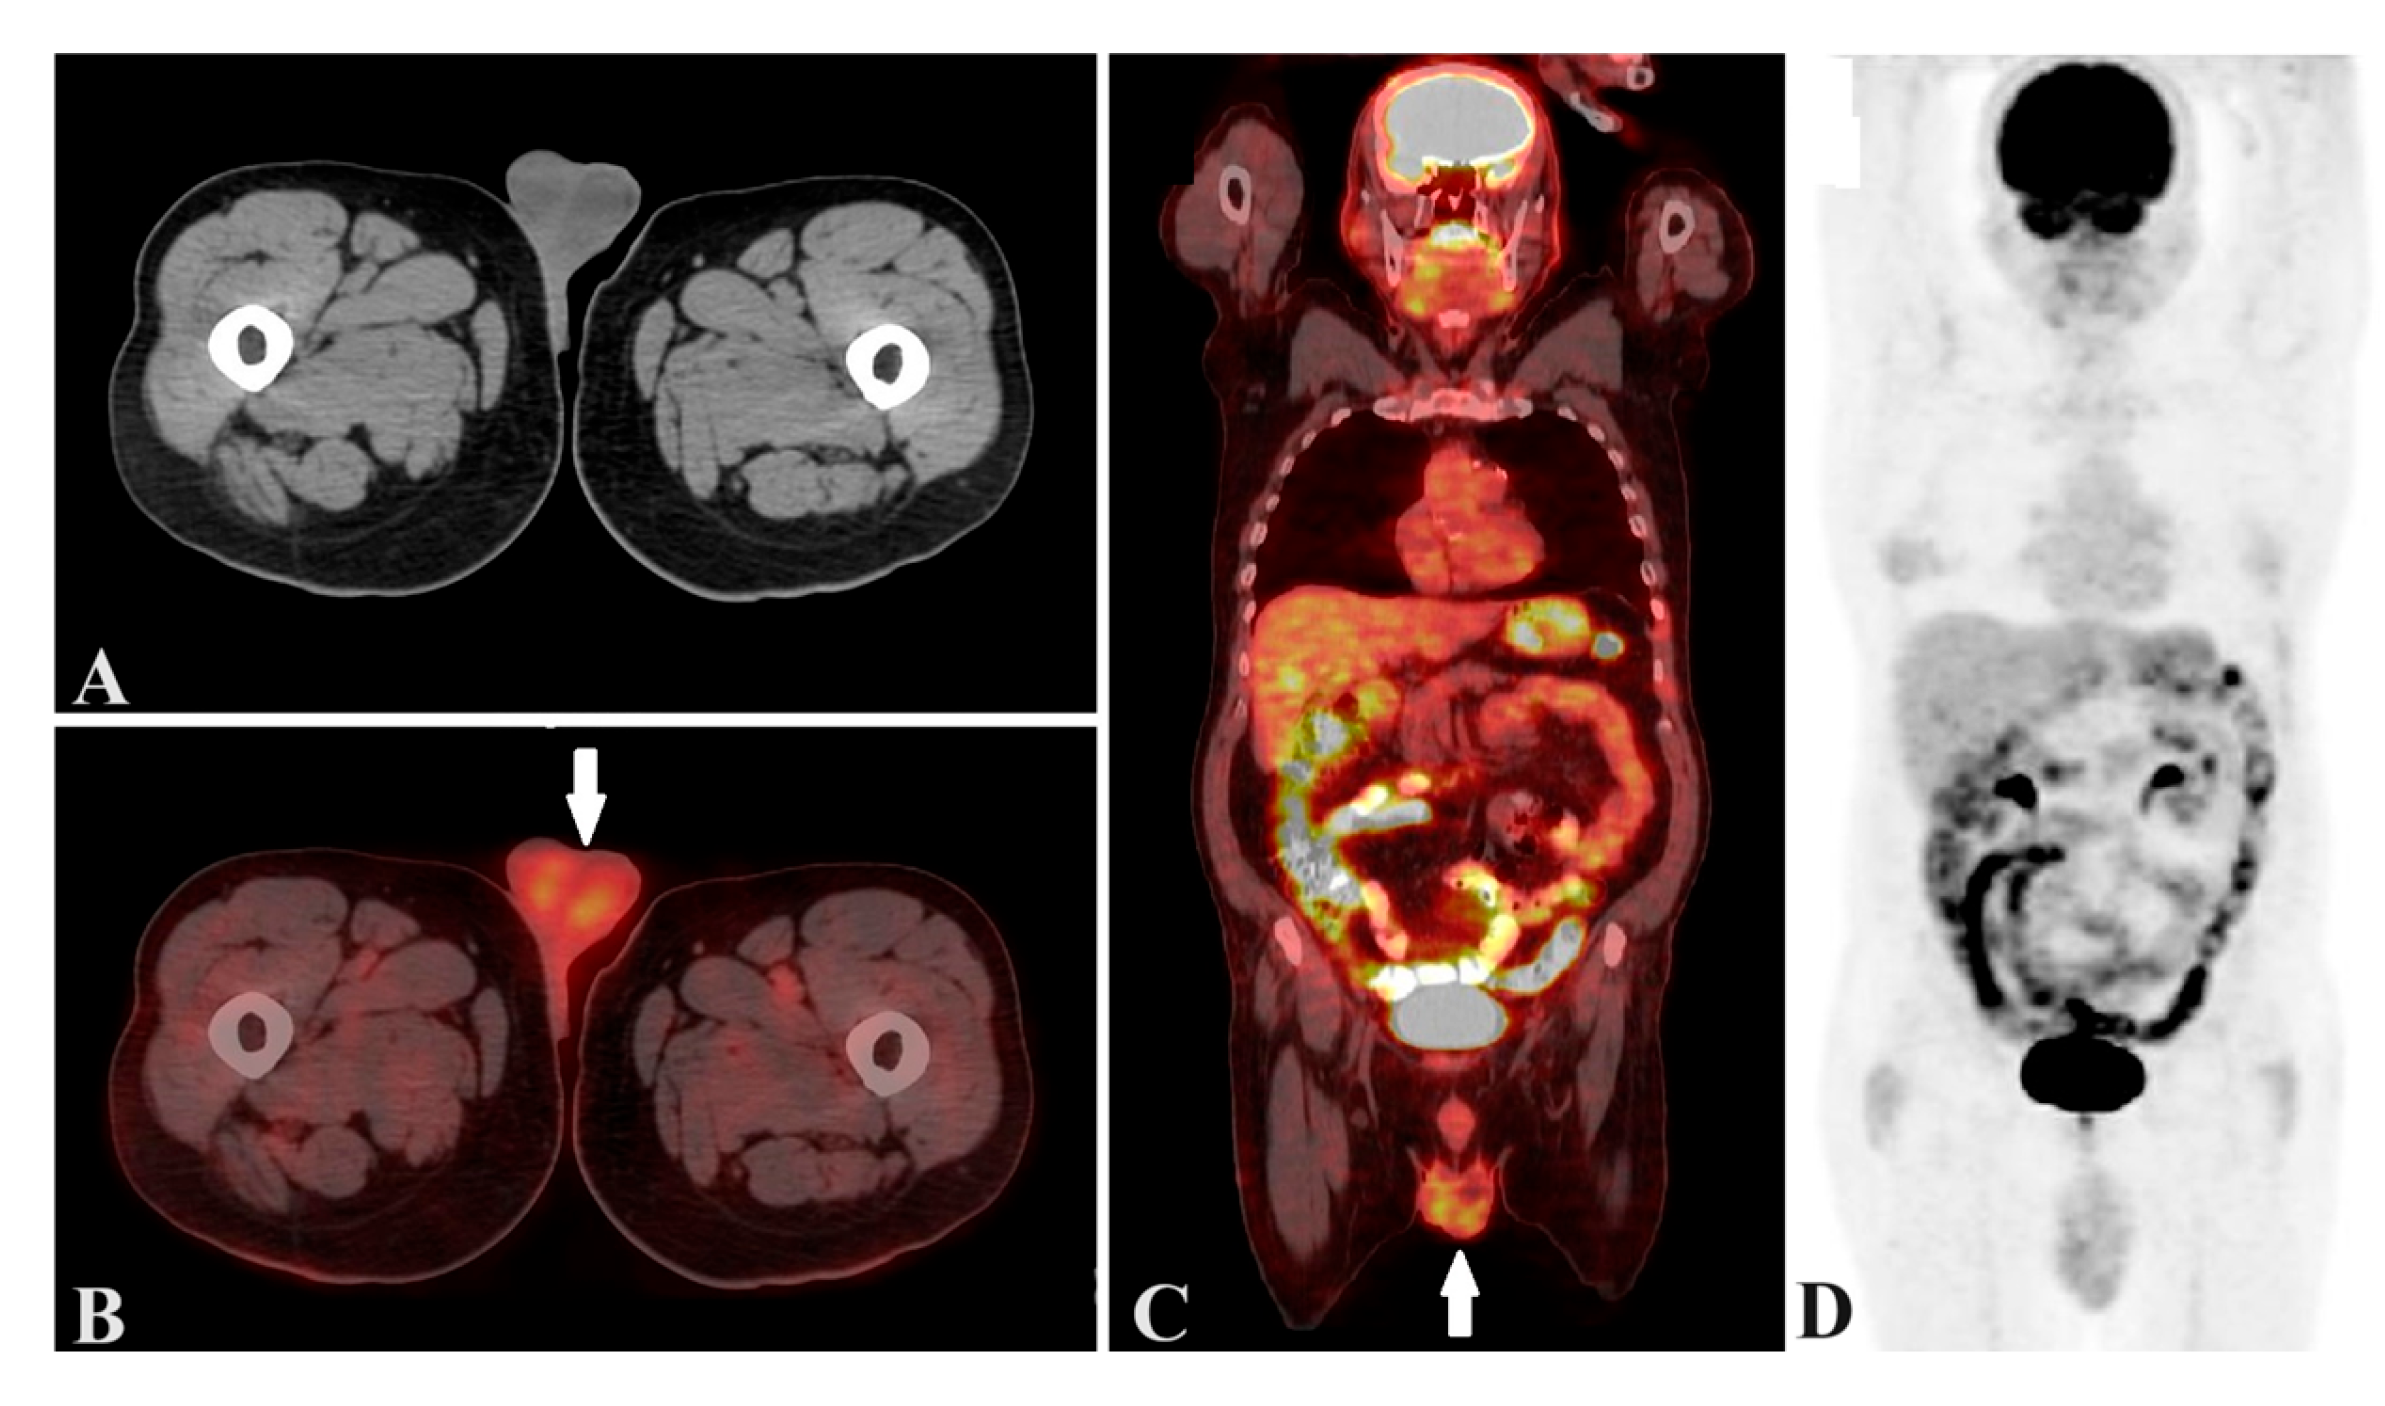

Figure 1. A 32-year-old man patient. A: Axial computed tomography image of testis. B: Axial PET/CT image of with symmetric testicular uptake of 18F-FDG (white arrow) C: Coronal PET/CT image of with symmetric testicular uptake of 18F-FDG (white arrow), and D: maximum intensity projection image. PET/CT=positron emission tomography/computed tomography, 18F-FDG=18F-fluoro-2-deoxyglucose.